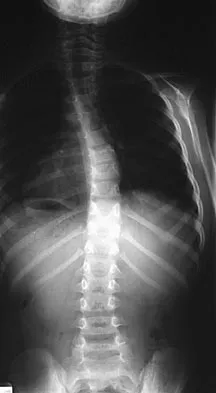

A 44-year-old woman has had lower extremity dysesthesias, urinary incontinence, and has been unable to walk for the past 2 days. She reports no pain or history of trauma. She notes that 3 weeks ago she missed work for 2 days because of back pain, but it resolved with rest. Examination shows decreased or absent sensation below the knees, no motor function below the knees, and decreased rectal tone. Catheterization results in a postvoid residual of 2,000 mL. Plain radiographs and MRI scans without contrast are shown in Figures 1a through 1d. What is the next most appropriate step in management?

Explanation

The patient has had a clear and sudden onset of a profound neurologic deficit. The radiographic studies suggest a lesion in the conus medullaris that appears to be intradural and intramedullary. MRI, with and without contrast, will best evaluate this mass further. The addition of gadolinium allows further evaluation of vascularity and the extent of the lesion. Eichler ME, Dacey RG: Intramedullary spinal cord tumors, in Bridwell KH, Dewald RL (eds): The Textbook of Spine Surgery, ed 2. Philadelphia, PA, Lippincott-Raven, 1997, vol 2, pp 2089-2116.